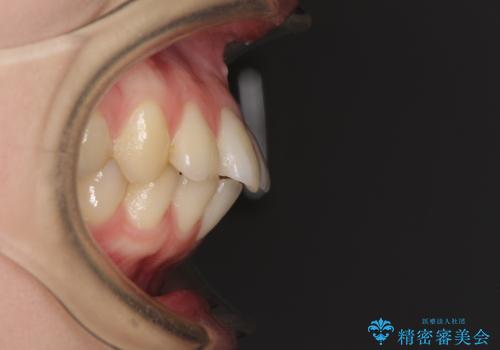

- 口元の突出感と口の閉じにくさを気にして来院された患者様です。

上下左右第一小臼歯4本を抜歯し、ワイヤー装置にて口元を引っ込めるよう矯正治療を行うこととしました。